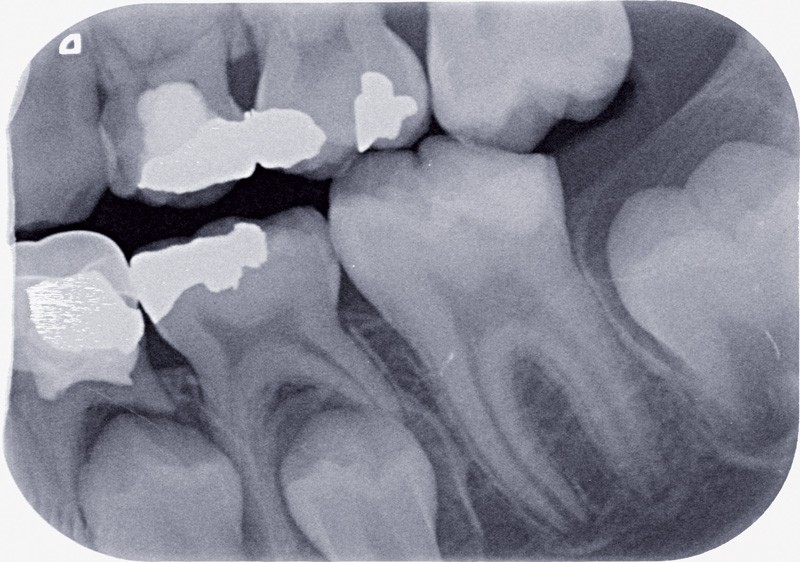

Immaturité amélaire

La période d’éruption de la dent, c’est-à-dire le laps de temps entre l’apparition des pointes cuspidiennes dans la cavité buccale et son occlusion fonctionnelle, est conséquente. Elle est par exemple de 15 mois en moyenne pour la première molaire et 27 mois pour…